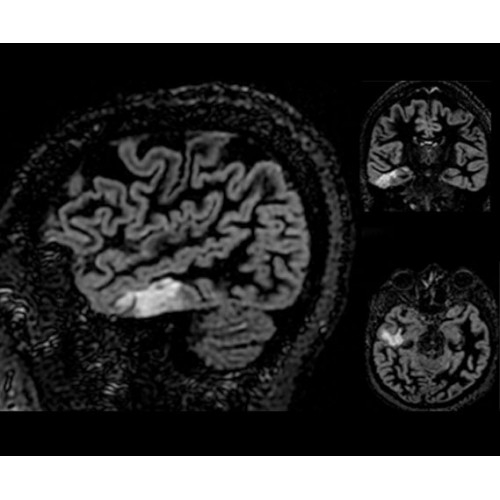

• NeuroWorks — универсальное решение для визуализации анатомии головного мозга, позвоночника, сосудов и периферических нервов с четкой дифференциацией тканей.

• SilentWorks — технология шумоподавления, которая снижает уровень шума для некоторых видов исследований до минимальных значений.